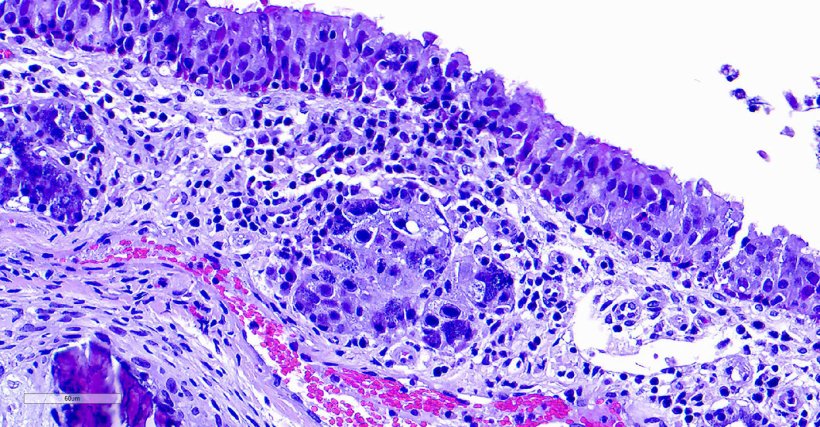

La rinitis por cuerpos de inclusión (IBR) está causada por el citomegalovirus porcino (PCMV). Esta enfermedad recibió su nombre debido a los característicos cambios histopatológicos observados en las células de la mucosa nasal de los cerdos afectados. Estos animales presentan cuerpos de inclusión intranucleares basófilos, principalmente en las glándulas submucosas, aunque también pueden hallarse en otros tejidos. Aunque el PCMV está ampliamente distribuido y presenta una elevada prevalencia en las poblaciones porcinas, su impacto en la industria porcina sigue sin estar claramente definido y suele ser subestimado, debido a las posibles interacciones con otros patógenos.